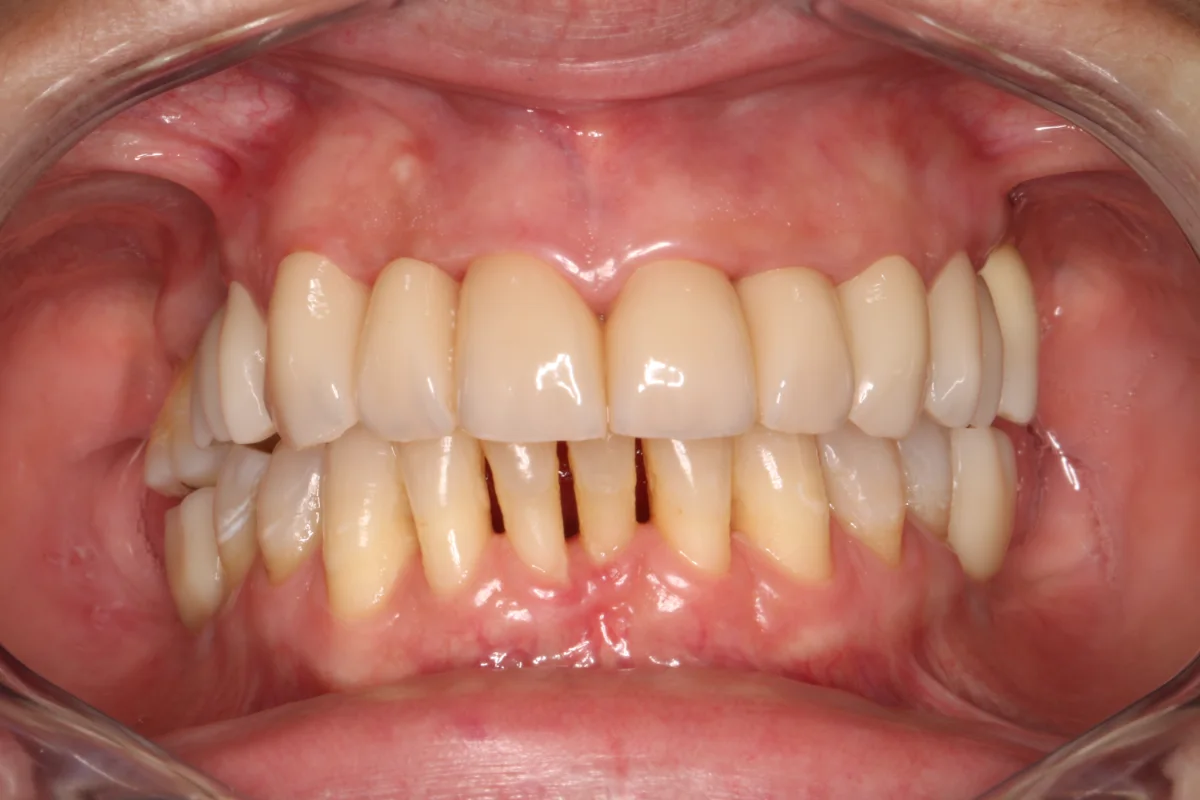

Siempre que el paciente reúna los requisitos clínicos adecuados, se irá con unas prótesis provisionales sobre los implantes que se colocarán en esa misma sesión.

Después Después